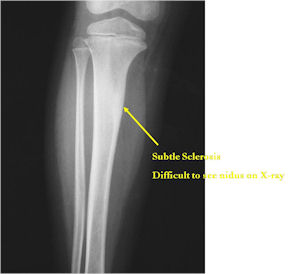

- Lucent nidus surrounded by a zone of marked sclerosis

- The nidus may demonstrate mineralization/ossification usually from the center outward that appears as a central zone of density within the nidus

- A nidus that is heavily ossified may blend in with the surrounding sclerosis and be difficult to detect on a plain x-ray.

- Periosteal bone is solid, rarely lamellated